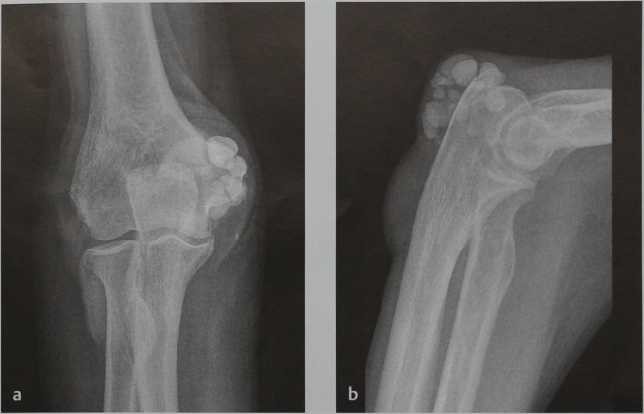

а, b Синовиальный хондроматоз локтевого сустава мужчины 30 лет: a) Прямая проекция; b) боковая проекция.

а-d Хондроматоз коленного сустава . Пациент 57 лет с рецидивирующим выпотом в коленном суставе: а, b) Рентгенологическое исследование в двух проекциях: множественные поражения в межмыщелковой и задней части коленного сустава.